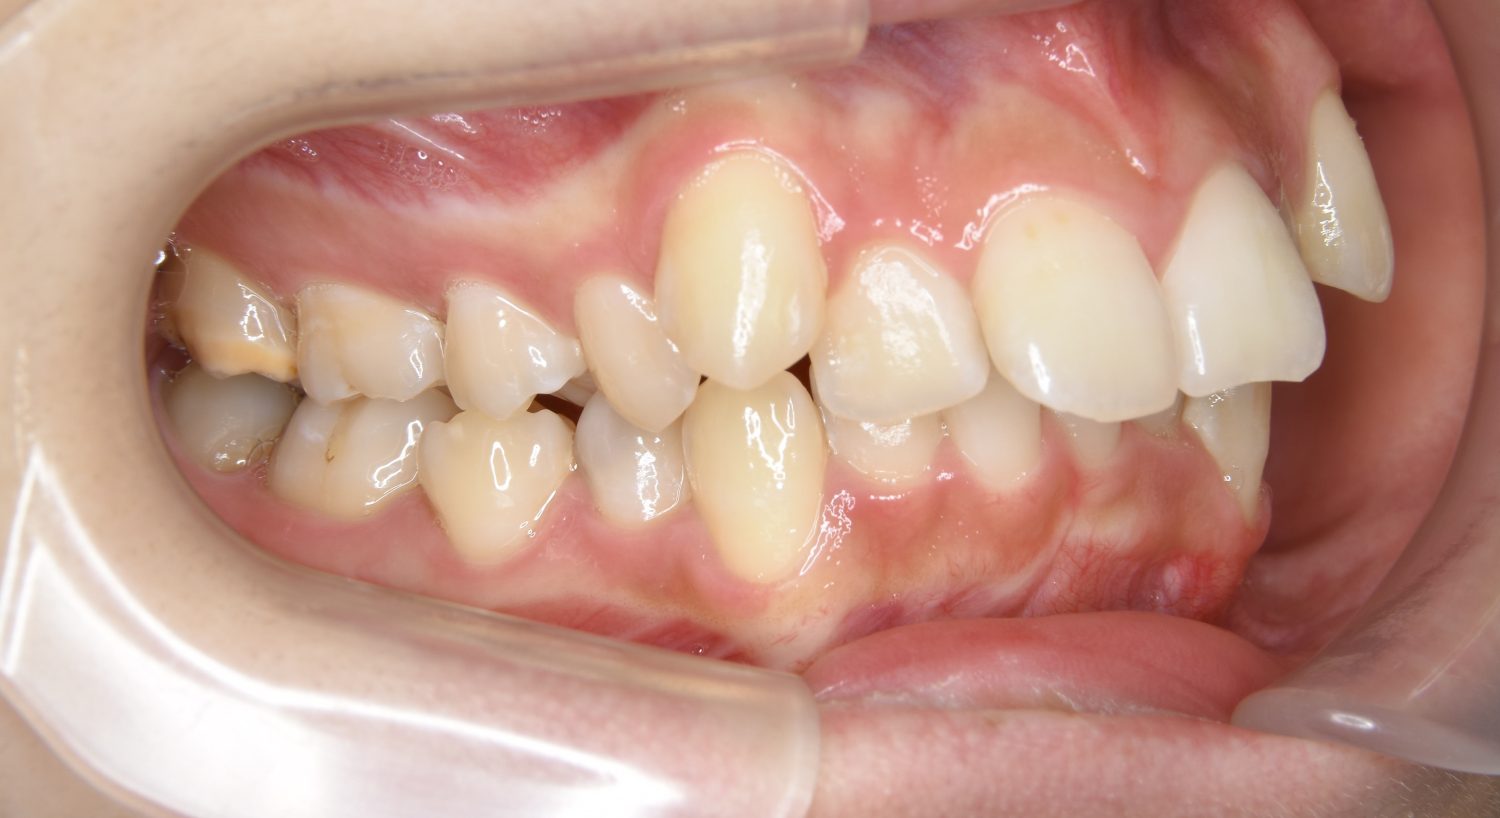

叢生の症例紹介②

Before

After

主訴

歯の凸凹を治したい。

治療内容

アライナー(インビザライン)にて非抜歯で治療を行いました。

治療費

1,150,000 円(税込)

治療期間

26ヶ月

通院回数

14回

想定されたリスク

※歯根吸収、歯肉退縮、歯髄壊死、顎関節症状

※アライナー(インビザライン)は日本の薬機法未承認の矯正装置であり、医薬品副作用被害救済制度の対象外となる場合があります。

丸山和宏先生

ピーススマイル矯正歯科

上下前歯部に叢生(凸凹)が認められる状態でした。歯列の遠心移動を行うことで機能面および審美面が改善されました。